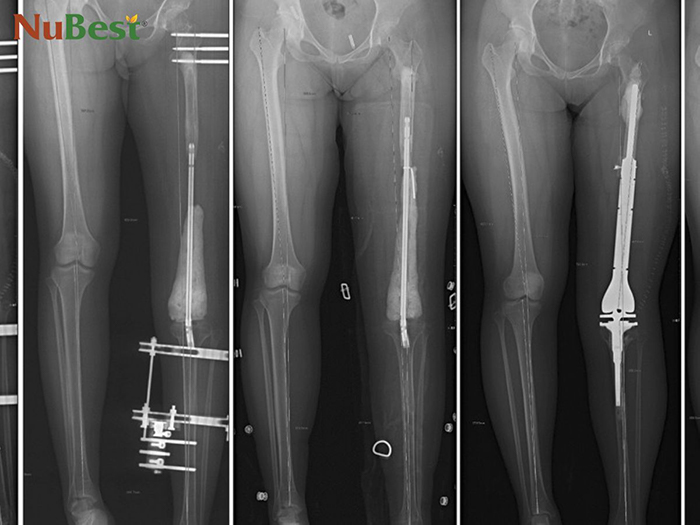

Với những người trưởng thành, trong độ tuổi từ 20-35, vẫn có thể tăng thêm chiều cao của mình nếu chấp nhận đau đớn và rủi ro để phẫu thuật kéo dài xương chân. Trong quá khứ, phương pháp này vốn được áp dụng để điều trị cho những chiến sĩ bị tổn thương xương khi tham gia chiến tranh, người bị tai nạn, dẫn đến chân dài chân ngắn. Theo thời gian, công nghệ phẫu thuật ngày càng được nâng cao, trong khi chiều cao lại được xem trọng, nên nó đã phát triển trở thành một phương pháp thẩm mỹ tăng chiều cao.

Phẫu thuật kéo dài xương rất đau đớn và nhiều rủi ro

Với cách tăng chiều cao cho người trưởng thành này, các bạn sẽ phải tham gia một cuộc phẫu thuật phần xương ở chân. Bác sĩ sẽ lắp các thiết bị chuyên dụng vào chân của bạn để cố định và điều chỉnh xương tăng trưởng. Cách này lợi dụng khả năng tự phục hồi của xương khi bị tổn thương để giúp 2 đầu xương bị tách dài ra, liền lại với nhau và giúp chiều dài xương tăng lên.

Về lý thuyết, phẫu thuật kéo dài xương có thể giúp bạn cao lên bao nhiêu tuỳ ý. Nhưng được khuyến cáo chỉ nên tăng thêm 6-8cm chiều cao để tránh làm cơ thể mất cân đối. Vì chỉ có xương chân dài ra, các xương khác đều như cũ, nếu kéo dài quá nhiều sẽ làm cơ thể bị mất cân đối.